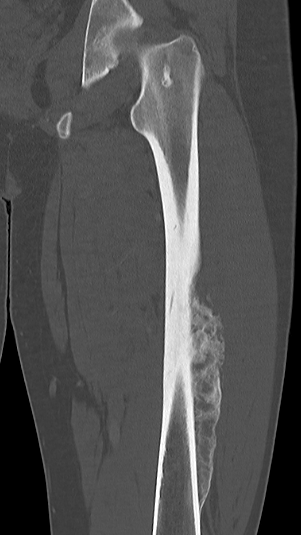

Ewing's femoral diaphysis, subtle on xray with large soft tissue component

CT

Pathological fracture with skip lesion